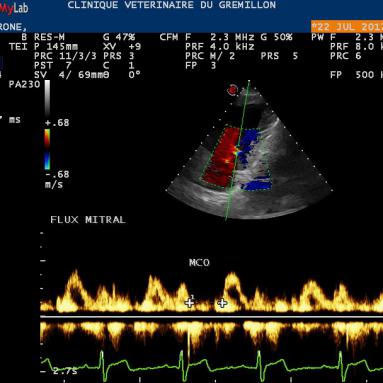

Les modes Doppler servent à visualiser et à mesurer les vitesses des flux de sang. Ils sont au nombre de trois:

• Le Doppler Couleur: il permet de visualiser les flux de sang dans un organe, la couleur (bleue ou rouge) permet d'orienter le sens du sang.

• Le Doppler Pulsé: ce mode permet de mesurer la vitesse du sang en un point précis sur une ligne que l'on place et que l'on oriente à notre guise. Ce mode est surtout utiliser pour s'assurer de l'efficacité d'un flux sanguin ...

IPM: Indice de Performance Myocardique (Methode dite des flux)

Pour effectuer sa mesure, il est necessaire de mesurer le temps entre deux flux mitraux et de le temps d'ejection systolique